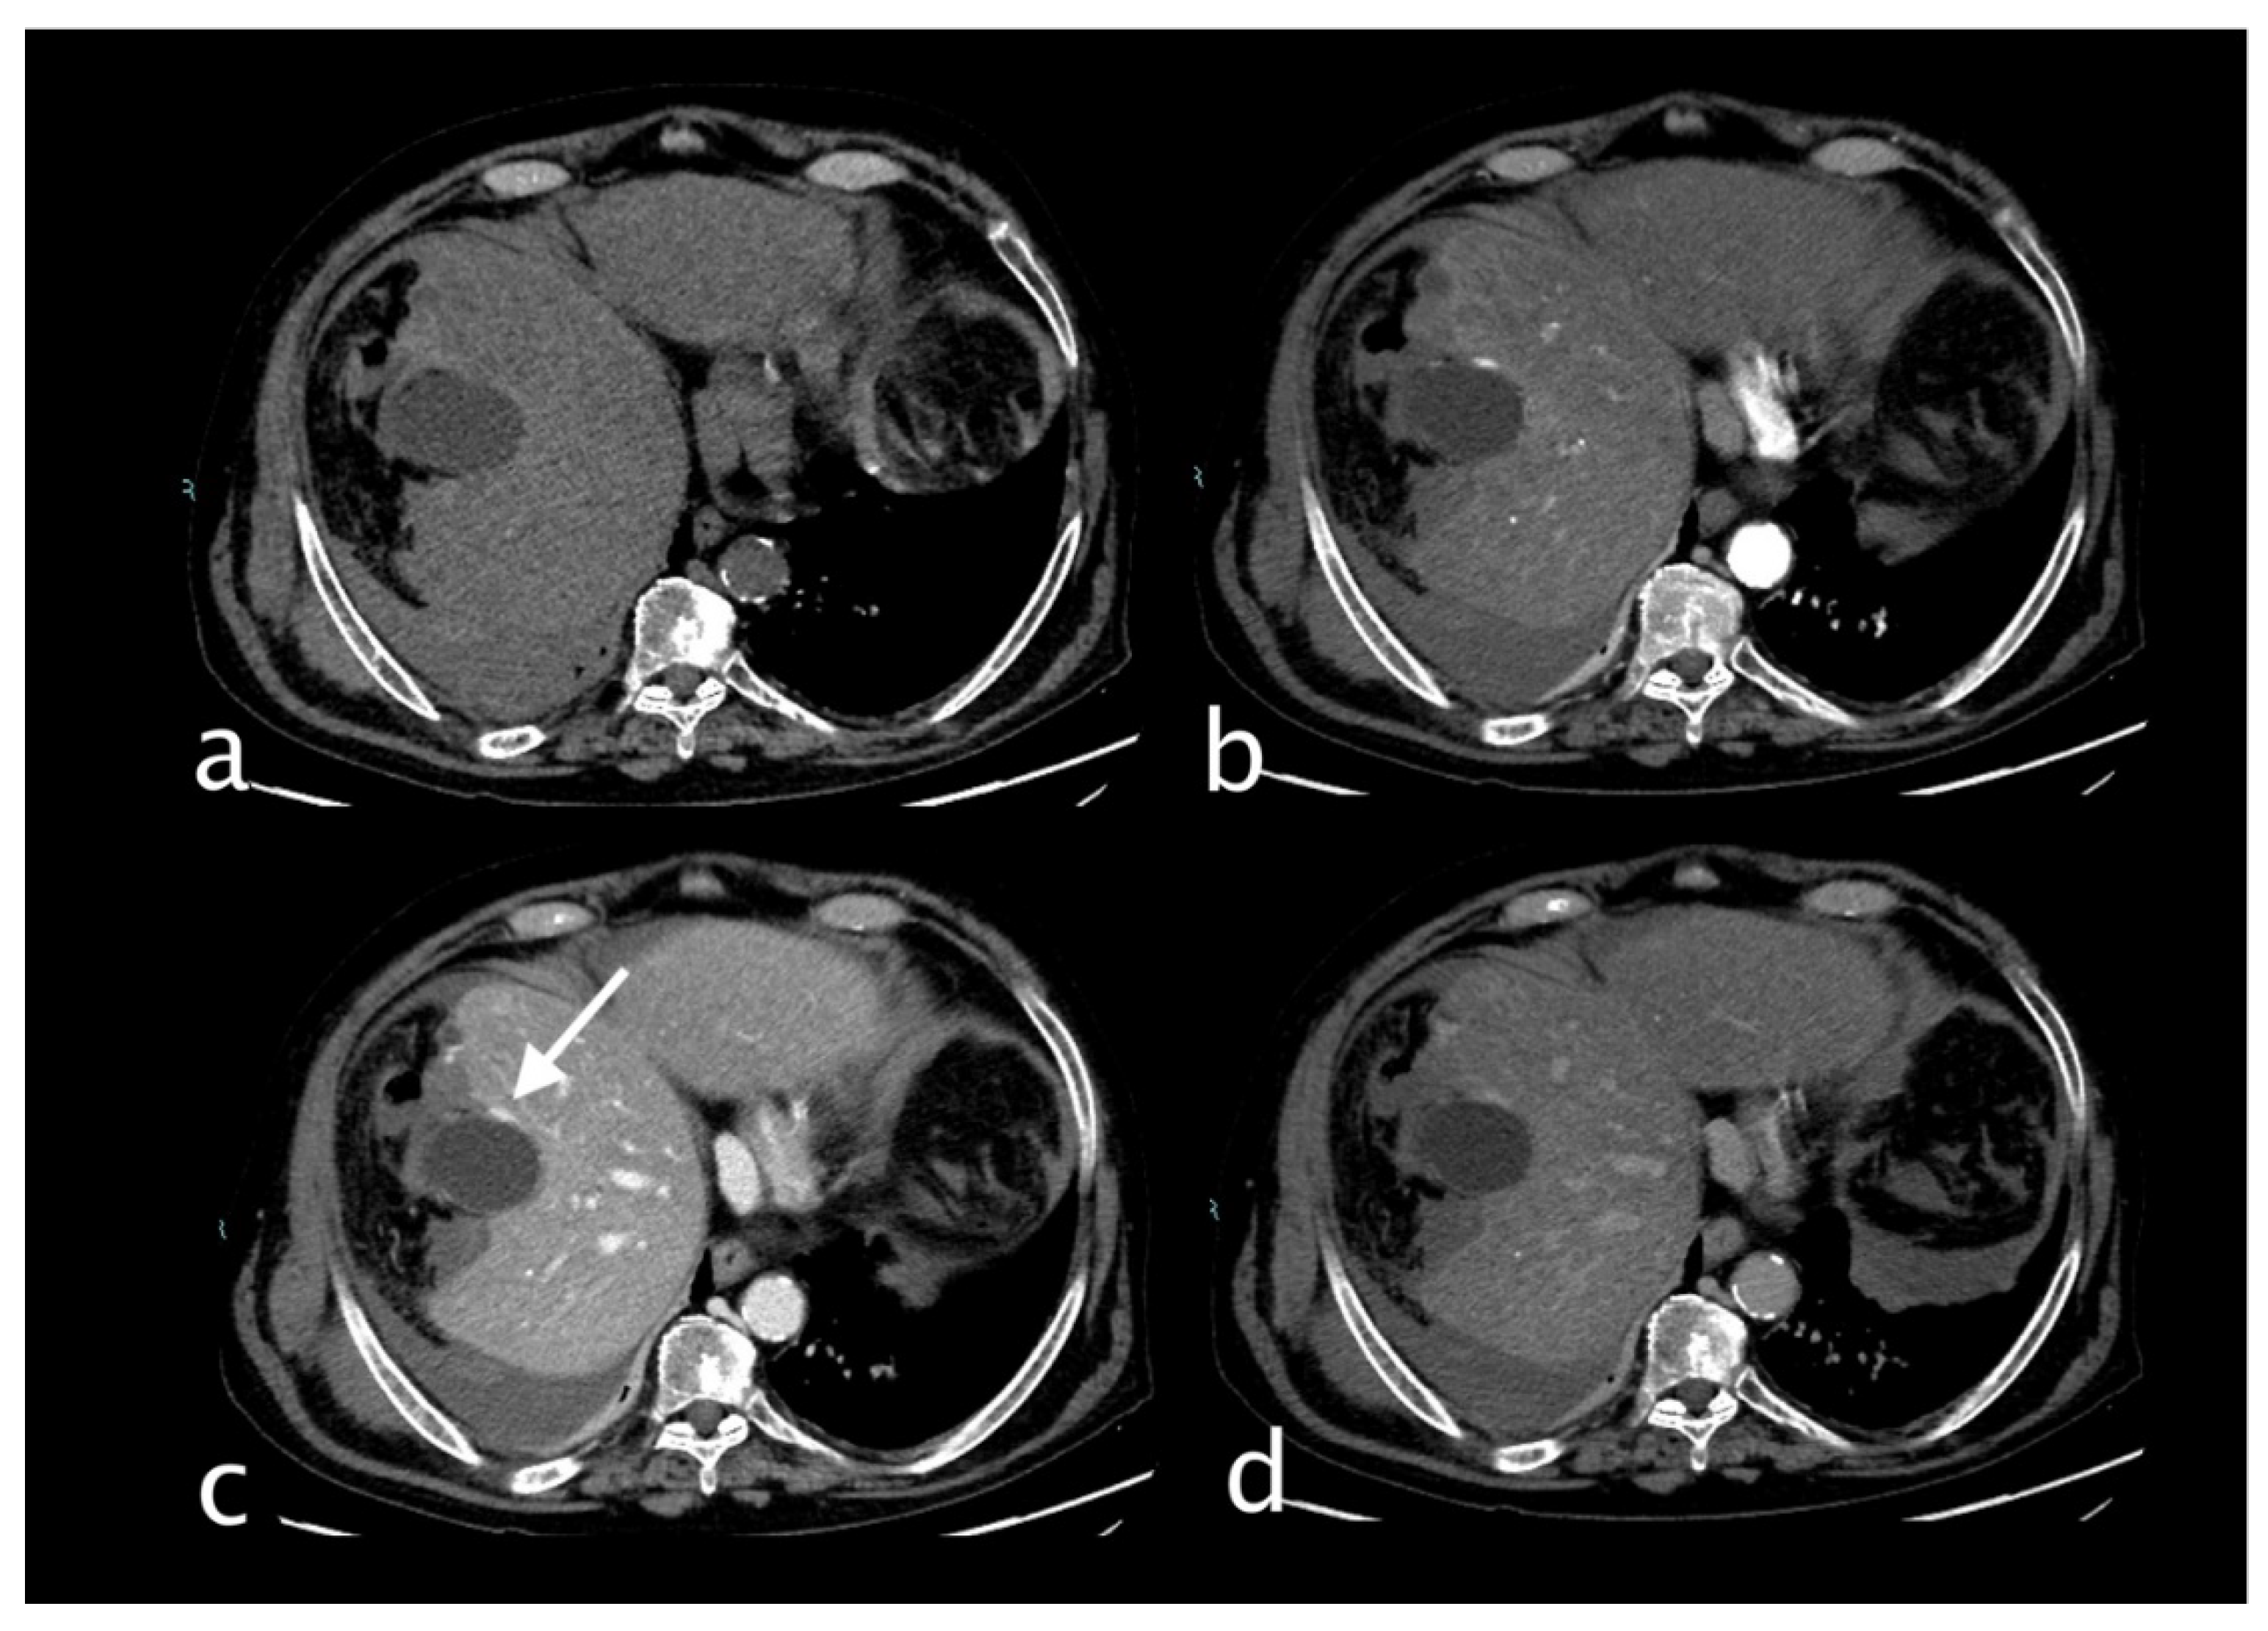

Imaging

TRAUMATIC CYSTIC ARTERY BLEEDING

Non-Traumatic and Iatrogenic Cystic Artery Bleeding